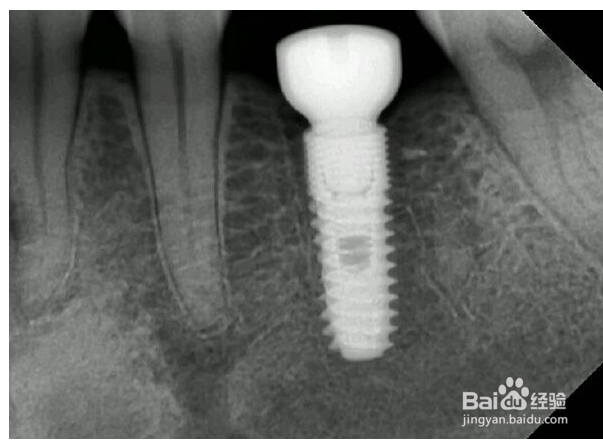

1、了解自身的情况,每个人牙齿的情况不一样,能用的材料就不一样,比方说有些患者牙槽骨比较薄,这样在植体选择上就要选一些有不同大小型号的植体,或者说有一些缺牙时间长,要选一些能够抑制骨吸收的植体

2、对于骨吸收,有些植体在骨与软组织接触的地方能形成一道屏障,既然防止细菌的进入,又能够防止骨吸收,这对于患者来说是很重要的功能

3、对于植体的材质,建议大家选用全肽类的,生物相容性好,另外有一些植体,为避免广告嫌疑我就不说哪个厂家的了,是使用的亲水性的表面材料,这样的材料在体内能够迅速与体内结构结合,省区了机体分解疏水性材质的时间,一般肯那个一个月就可以与骨完全结合了